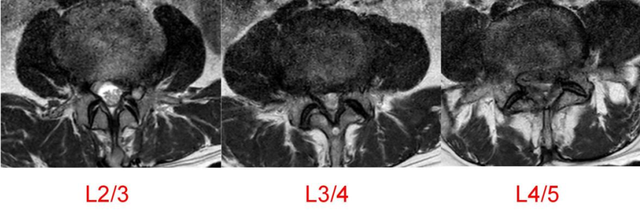

▲3D打印直观显示椎体结构,指导手术精准置钉

陈勇主任在医学3D打印技术团队的支持下,通过术前采集患者目标椎体的三维信息,运用3D打印技术重建脊柱三维模型,设计椎弓根螺钉的置入钉道,有效控制置钉的位置、方向及角度,从而提高置钉的准确性和成功率,以减少术中置钉过程中神经损伤的风险。

▲术中椎弓根螺钉精准置入

▲术后复查X线、CT